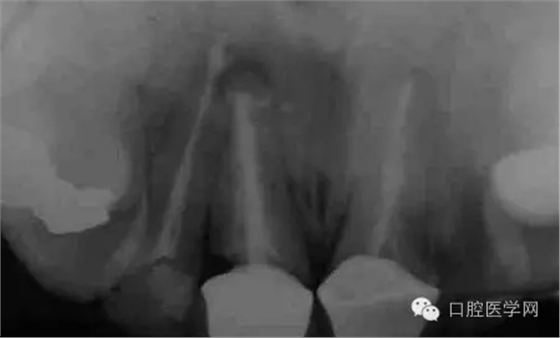

圖1 X線顯示上11根尖息肉陰影